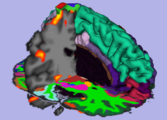

Result from the ARCTIC module in Slicer 3.6: cortical thickness map from pediatric MRI